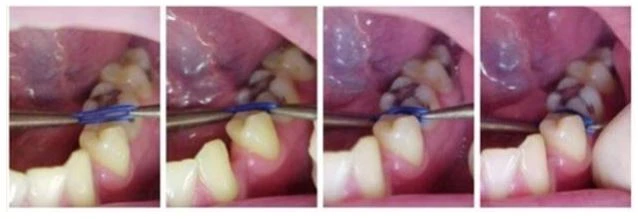

Cách đặt chun tách khe:

a. Bằng kìm đặt chun: Nhẹ nhàng, nhanh, ít gây khó chịu cho bệnh nhân nhất.

b. Dùng chỉ tơ:

c. Dùng kẹp Mosquito